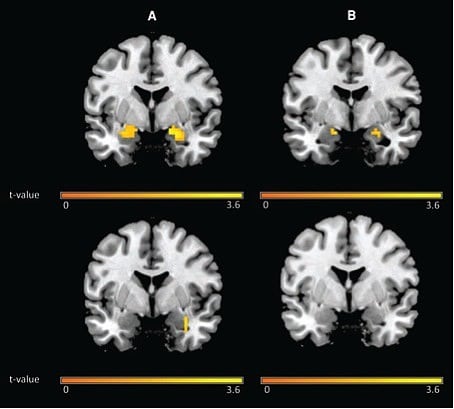

Einen weiteren Tag später sahen die Probanden die Fotos wieder, während ihre Hirnaktivität in einem Magnetresonanztomografen aufgezeichnet wurde. Probanden mit sechsstündiger Wartezeit am Vortag zeigten noch eine schwache Angst, wenn sie die "Schock-Lampe" sahen. Ihre Amygdala - die Emotionszentrale des Gehirns - war außerdem stärker aktiviert als bei den Versuchspersonen der Zehn-Minuten-Gruppe, die das Bild nun kalt ließ.